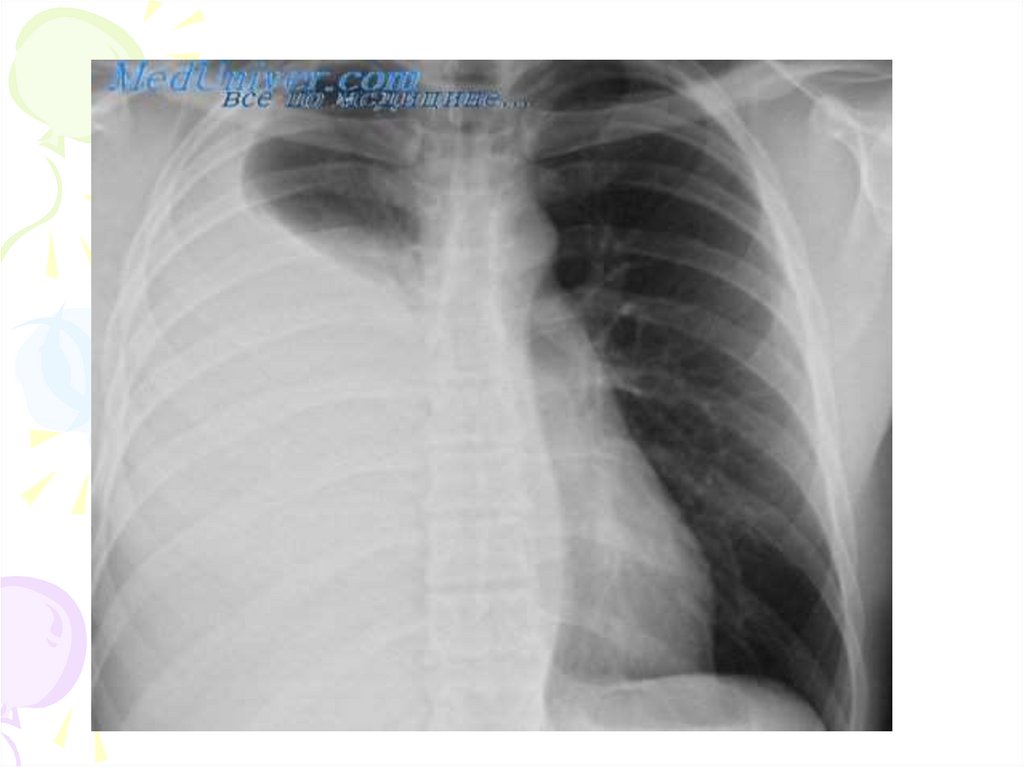

Очаговая пневмония

16.